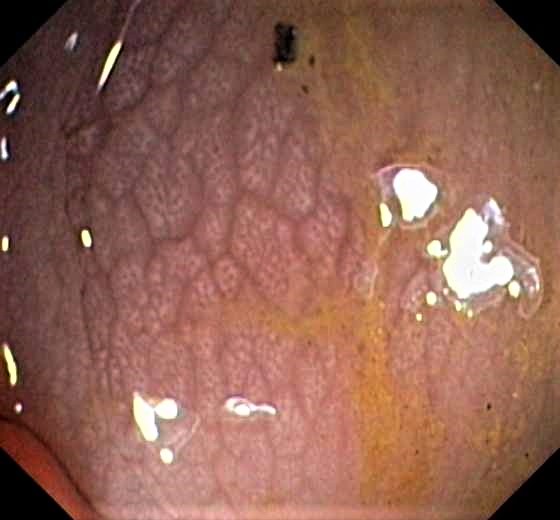

Colon Cancer (Adenocarcinoma) with Chicken Skin Mucosa

Slight Mucosal Changes are frequently seen adjacent to a colorectal cancer or adenoma. First described by Shatz BA et al, they are called Chicken Skin Mucosa (CMS), and are supposed to occur as a result of fat accumulation in macrophages in the lamina propria adjacent to colonic neoplasms. In a series of 852 consecutive colonoscopies CMS was found adjacent to eight of 10 distal colorectal cancers, one of four of proximal colon cancers and 16 of 42 distal adenomas.